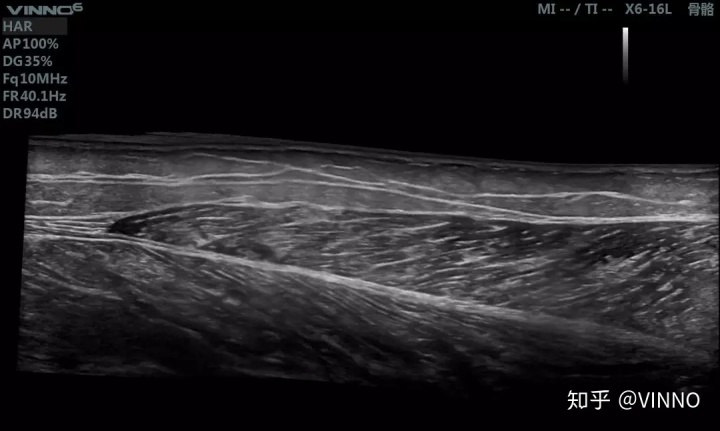

▲ 这是超声扫描影像

成像原理:用超声波穿透人体,当声波遇到不同的组织会产生反射波,超声探头一面发出超声,一面接受反射波,通过计算反射波成像。